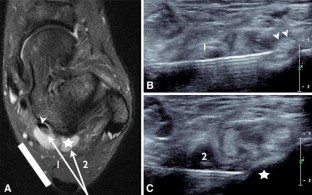

Fig. 2